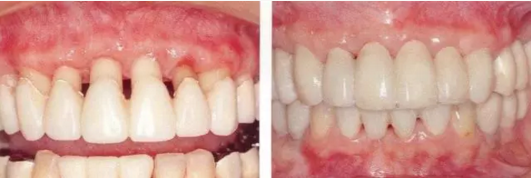

▲圖19-8,9

▲圖19-8  佩戴臨時修復(fù)體。即使在這個狀態(tài)下,依然有牙周袋殘留。

▲圖19-9  完成牙周外科治療后的狀態(tài)。

▲圖19-10,11

▲圖19-10  牙周外科治療后3周的狀態(tài)。從照片可見牙周袋的去除量。

▲圖19-11  數(shù)月以后,對臨時修復(fù)體進行修整后的狀態(tài)。

佩戴最終修復(fù)體時的正面照片。